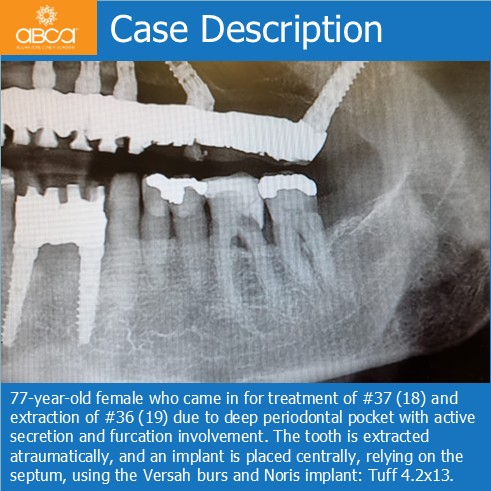

77-year-old female who came in for treatment of #37 (18) and extraction of #36 (19) due to deep periodontal pocket with active secretion and furcation involvement. The tooth is extracted atraumatically, and an implant is placed centrally, relying on the septum, using the Versah burs and Noris implant: Tuff 4.2×13.